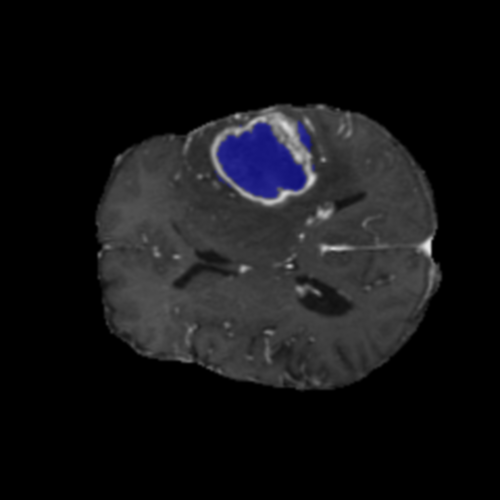

Ejemplos LGG - Atención Difusa en Edema Peritumoral

LGG Grad-CAM++ 1 LGG Grad-CAM++ 2 LGG Grad-CAM++ 3 LGG Grad-CAM++ 4 LGG Grad-CAM++ 5 LGG Grad-CAM++ 6

Para casos LGG, la atención del modelo es más difusa y se concentra principalmente en la región de Edema Peritumoral (verde), consistente con la naturaleza más infiltrativa y menos agresiva de estos tumores.